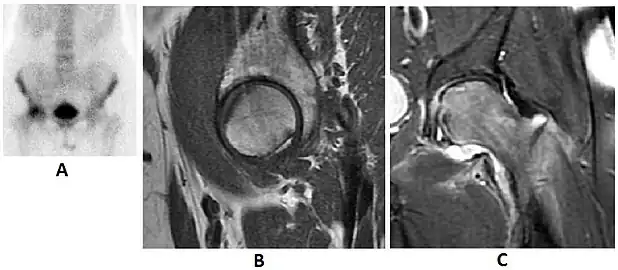

Radiological signs of transient osteoporosis of the hip include localized osteoporosis of the femoral head and neck (Figure 8). Nevertheless, final diagnosis has to be made with MRI to differentiate it from avascular necrosis and from insufficiency or stress fractures of the femoral head or neck. In case of AVN, radiographs can only demonstrate delayed or advanced signs. Staging according to Ficat classification ranges between normal appearance (stage I), slight increased density in the femoral head (stage II), subchondral collapse of the femoral head with or without “crescent” sign (stage III), and advanced collapse with secondary osteoarthritis (stage IV). In the case of stress or insufficiency fractures X-ray sensitivity has been proven to be much lower than MRI, which is currently the gold standard.[1]

Figure 8:

-

X-ray of a patient with transient osteoporosis of the left hip showing osteoporosis.[1] -

Coronal stir imaging in transient osteoporosis, showing diffuse edema.[1] -

Scintigraphy (A), sagittal T1 (B), and coronal PD fat sat of a patient with a subchondral fracture of the femoral head with convex shape to the articular surface.[1] -

Coronal T1 of a patient with avascular necrosis of the femoral head.[1]

Intra-articular osseous causes of pain include several conditions: avascular necrosis (AVN), transient osteoporosis of the hip (TOH), tumors, and stress or insufficiency fractures. All these entities may present with a pattern of bone marrow edema characterized by decreased signal intensity on T1 weighted images and increased signal intensity on fluid sensitive sequences, such as fat saturated T2-weighted or STIR images. When there is no evidence of a focal lesion associated with the edema pattern, TOH is suspected. When a band of low intensity is seen inside the edematous area, the shape and length of this band become important. It is generally convex to the articular surface in the case of subchondral stress or insufficiency fractures, whereas it is concave, circumscribing all of the necrotic segment, in cases of AVN. When doubts do persist, gadolinium-enhanced MRI tends to show that the proximal portion beyond the band is enhanced in fractures but is not in AVN.[1]